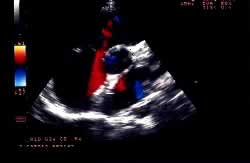

È suscettibile di chiusura percutanea transcatetere il difetto interatriale ostium secundum “tipo fossa ovale” (Figura 1). Le indicazioni alla chiusura sono le stesse della chirurgia. Possono essere chiusi, con il dispositivo di Amplatz, difetti anche molto ampi (diametro “stretched” fino a 40 mm) purché con caratteristiche anatomiche favorevoli: distanza tra margine del difetto (rim) e vena polmonare superiore destra, seno coronarico, vena cava superiore, vena cava inferiore e valvole atrioventricolari di almeno 5 mm. Le controindicazioni alla chiusura percutanea sono riportate in Tabella 1.

La procedura di impianto viene eseguita in anestesia generale con intubazione del paziente. Un ruolo essenziale, in tutte le fasi della procedura, è svolto dall’ecocardiografia transesofagea. Essa detta le indicazioni alla “fattibilità” (diametro del difetto, misura dei rims settali, ritorni venosi, anatomia atriale), guida l’operatore nel posizionamento della protesi a cavallo del difetto e nel successivo rilascio della stessa, permette una immediata valutazione del risultato (“tenuta” del device dopo rilascio, shunt residuo) (Figure 1, 3, 4). Dall’ottimale utilizzo e dall’esatta interpretazione dei dati forniti dall’ecocardiografia transesofagea dipende in larga parte la riuscita della procedura. Alcuni Autori riportano l’impiego di altri sistemi di monitoraggio durante la procedura quale ad esempio l’ecocardiografia intracavitaria (49). Quest’ultima consentirebbe di evitare l’uso dell’ecocardiografia transesofagea e quindi la necessità dell’intubazione.